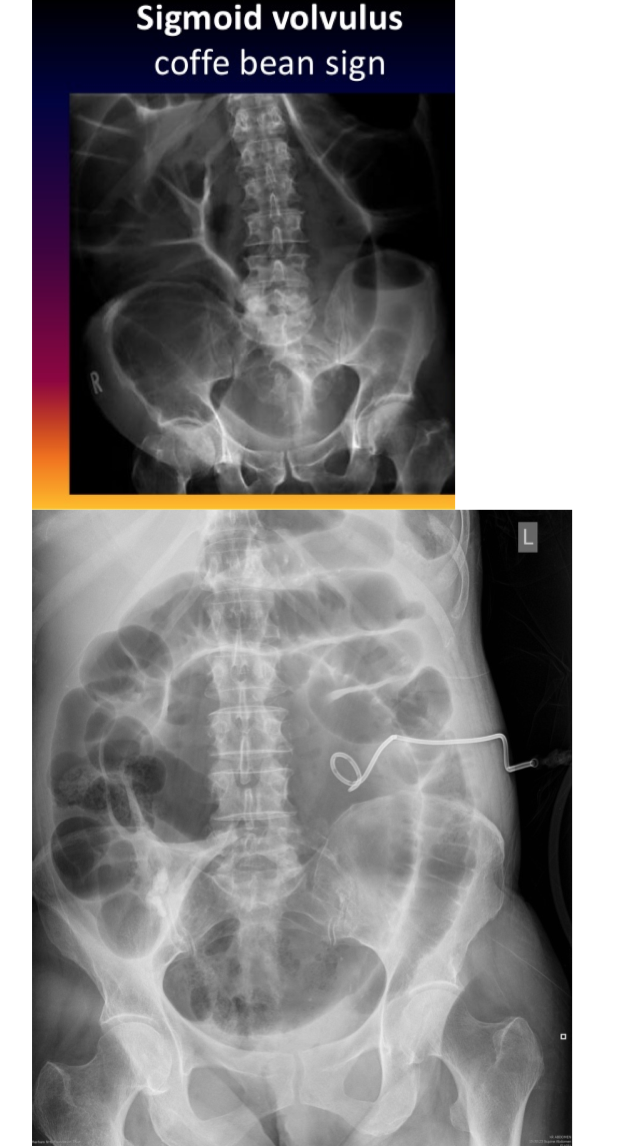

AXR-coffee bean sign